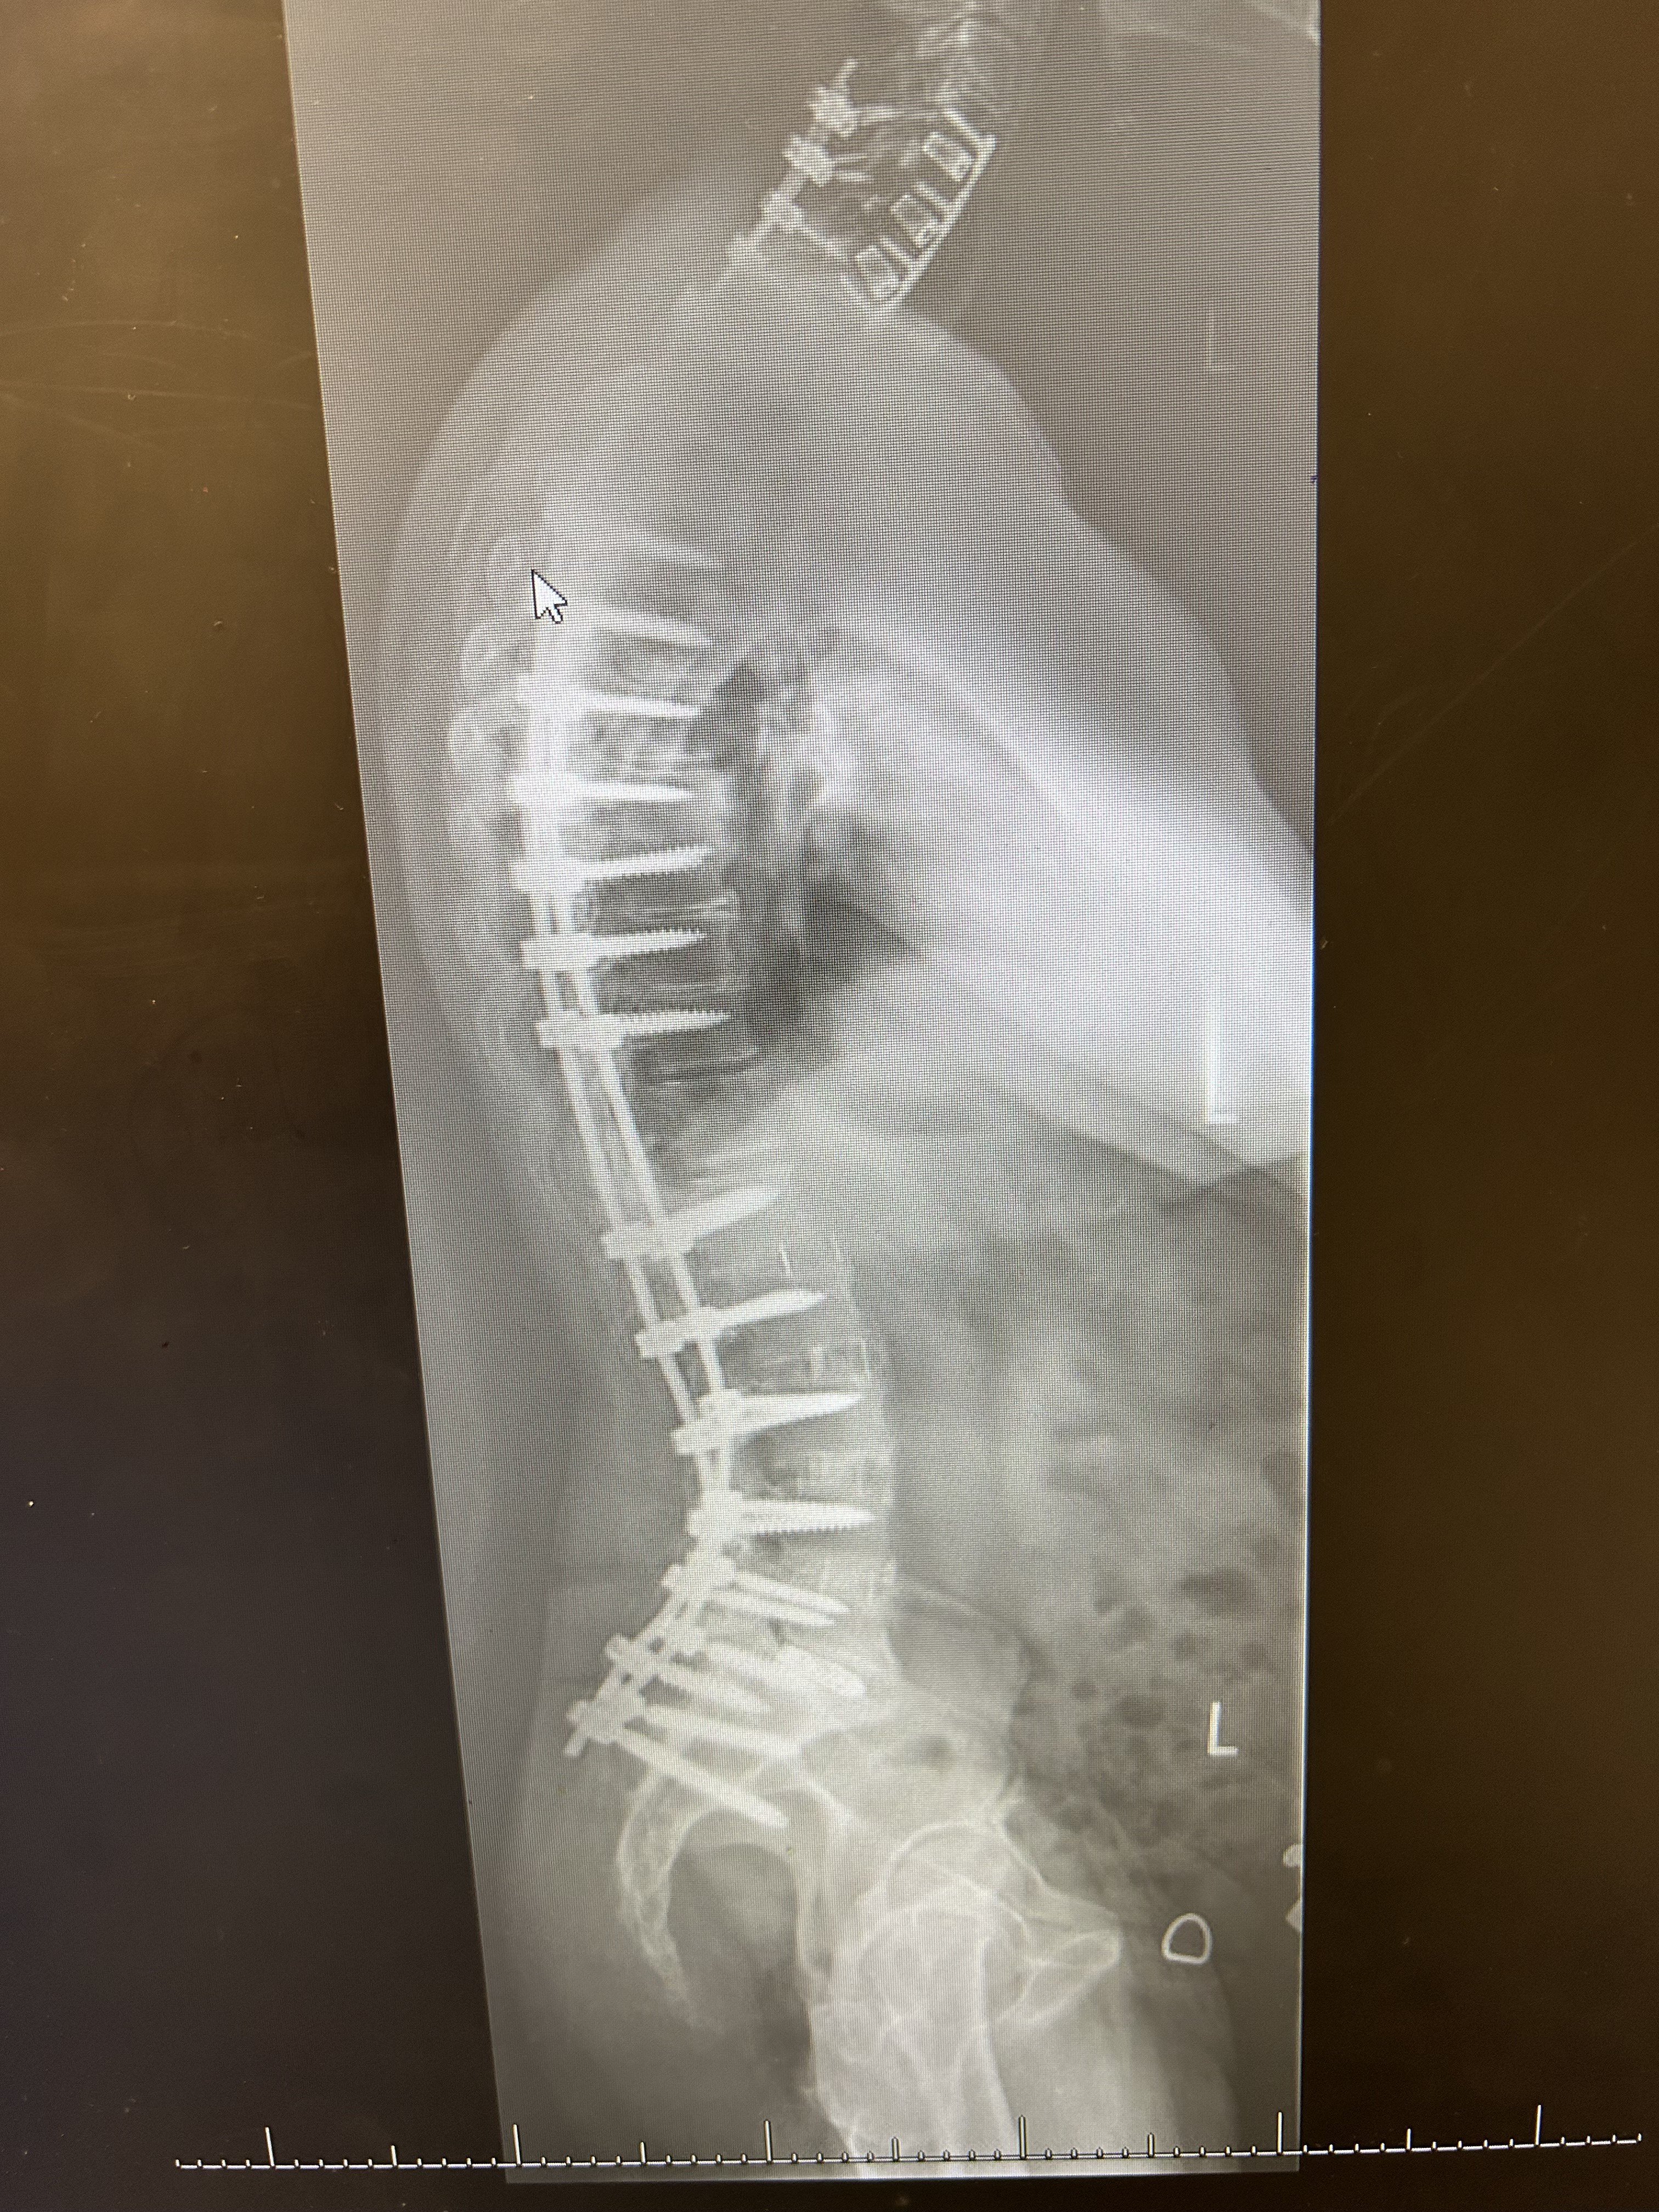

Yul Lose Posted February 1 Posted February 1 Best of luck to you. Times and procedures have changed a lot since my first 12 vertebrae were done in 1979 and 21 vertebrae, including the first 12 were fused and instrumented in 1992. I was in a body cast in 1979 for 4 months and then a back brace for 18 months after that. In 1992 I had so many complications that they put me in a medically induced coma for 2 months. They cleaned out the old fusions and discs and the other 9 discs and were going to go in the next day and do the fusions and install the hardware but I started having breathing issues and they couldn’t go back in to finish up for 5 months. So I laid in bed in a kydex jacket trying to get strong enough for them to finish. I was tube fed for nearly 3 months and had to learn how to talk, swallow and walk again. Both of the latter procedures were anterior and posterior approaches so they opened me up from tail bone to neck and across my abdomen both times. Recovery took many months. A lady that I shoot with just had 11 vertebrae done and her recovery was much faster. My surgeon told me that between my side to side and front to back curvature (scoliosis) I had 94 degree curvature, he said it was the worst he'd ever attempted to repair. Listen to and follow all of the advice that your surgeon and therapists give you, you’ll be glad you did. My X-rays. 1 2 Quote

Texas Maverick Posted February 1 Author Posted February 1 1 hour ago, Yul Lose said: Best of luck to you. Times and procedures have changed a lot since my first 12 vertebrae were done in 1979 and 21 vertebrae, including the first 12 were fused and instrumented in 1992. I was in a body cast in 1979 for 4 months and then a back brace for 18 months after that. In 1992 I had so many complications that they put me in a medically induced coma for 2 months. They cleaned out the old fusions and discs and the other 9 discs and were going to go in the next day and do the fusions and install the hardware but I started having breathing issues and they couldn’t go back in to finish up for 5 months. So I laid in bed in a kydex jacket trying to get strong enough for them to finish. I was tube fed for nearly 3 months and had to learn how to talk, swallow and walk again. Both of the latter procedures were anterior and posterior approaches so they opened me up from tail bone to neck and across my abdomen both times. Recovery took many months. A lady that I shoot with just had 11 vertebrae done and her recovery was much faster. My surgeon told me that between my side to side and front to back curvature (scoliosis) I had 94 degree curvature, he said it was the worst he'd ever attempted to repair. Listen to and follow all of the advice that your surgeon and therapists give you, you’ll be glad you did. My X-rays. All I can say is wow, glad it has all worked out for you. TM 1 Quote